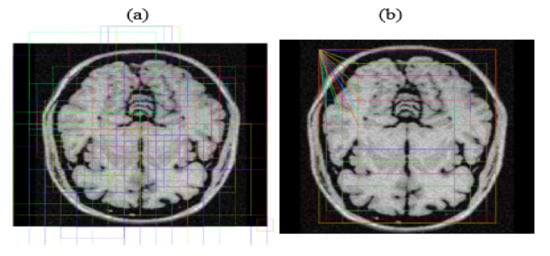

3.6. Creation of Anchor Boxes

The system identified Regions of Interest (RoIs) having targeted objects with significantly high probability from extracted feature maps by implementing a Region Proposal Network (RPN). RPN scanned brain MR images using the sliding-window technique to detect targeted objects. Rectangular boxes, called anchor boxes, cover a large part of the targeted object. Several weights applied on anchor boxes produced two outputs, classes and boxes. In this study, the anchor class is binary, either positive or negative. The positive response represents the presence of the brain inside anchor boxes, while the negative response represents background information such as non-brain parts. We derived the anchor class by calculating the intersection over the union (IoU) of ground truth with the anchor box. The threshold value for acceptable IoU ≥ 0.7, which shows that all positive anchors meet the benchmark criteria. Consequently, object classification transferred only positive anchor boxes with the brain in the foreground. At this level, the probability coefficient of each anchor box shows a high chance for occurrence of the brain. RPN further refined anchor boxes, shifting their position slightly and resizing them a little to fit over the brain. RPN takes derivative values to estimate changes in the anchor box. Figure 8 depicts two outputs wherein (a) shows positive anchor boxes and (b) shows refined and regressed anchor boxes, while Figure 9 depicts a histogram of derivatives of Region Proposal Networks.

Figure 8. (a) Positive anchor boxes; (b) refined and regressed anchor boxes.